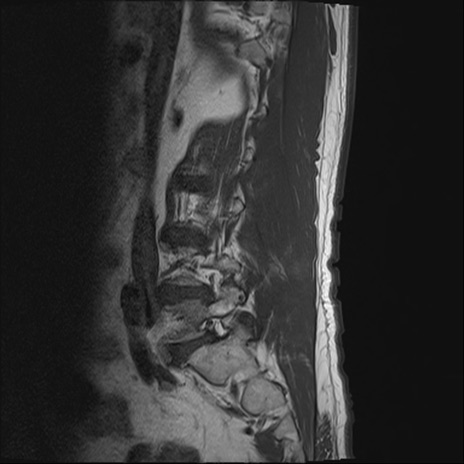

【整形】TIPS症例2 腰椎MRI T1WI(矢状断像)

【症例】70歳代男性

【主訴】左下肢痛

【現病歴】2週間前くらいから腰痛、左下肢痛あり。左臀部から大腿、下腿外側のしびれが常時ある。歩行とともに同部位の痛みあり。

【身体所見】Lasegue70-/60+、Bragard-/±、PTR ±/±、ATR -/-、IP 5/5、TA 5/4、TS 5/5、EHL 右第1足趾なし/3、FHL 5/5、hypersthesia(-)、足背動脈触知良好

異常所見と診断は?